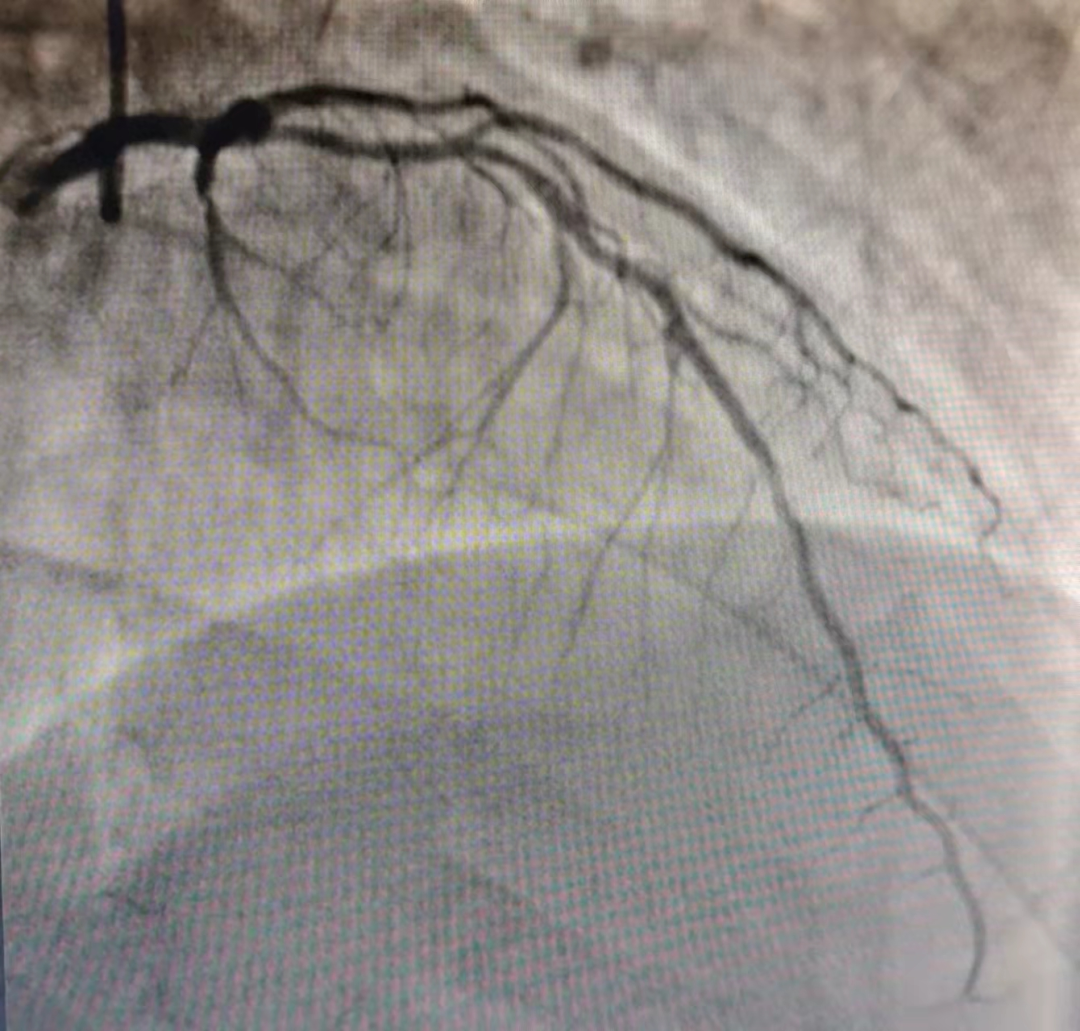

病例一:患者 80 岁,1 个月前出现阵发性剑突下堵塞感,与活动无明显相关。行冠脉造影检查提示左主干狭窄 50%,前降支中段狭窄 60-70%,回旋支、右冠脉大致正常。按造影结果左主干需行冠脉介入治疗。因症状不典型,行血管内超声检查提示左主干管腔面积 10.78 mm2,给予药物保守治疗,避免了左主干支架植入,避免了术中及术后风险。

病例二:患者 56 岁,1 个月前出现发作性胸骨后疼痛,向左肩背部放散,伴有胸闷、气短,多劳累时出现,每次持续几分钟后缓解,典型心绞痛。完善冠脉造影检查,结果示前降支近段狭窄 80%,累及左主干可能,回旋支及右冠脉大致正常。进一步行血管内超声检查,前降支近段斑块负荷 79%,开口斑块负荷 47%,斑块延展至左主干,因左主干与前降支管腔直径差距较大,于前降支局部病变植入支架 1 枚,术后血管内超声示支架贴壁良好、支架膨胀完全、无夹层。

病例三:患者 47 岁,8 年前出现发作性胸闷、气短、心前区针扎样疼痛,症状不典型。入院后行冠脉造影检查,提示前降支弥漫性病变,中段最重处狭窄 60%,远段狭窄 30-40%,回旋支远段狭窄 90%,右冠脉狭窄 40-50%。于前降支病变处行血管内超声检查,最重处斑块负荷 61%,为临界病变,不需要冠脉介入治疗。回旋支病变处行经皮冠状动脉药物球囊扩张成形术,效果良好。